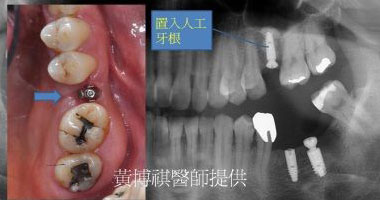

一般而言,口腔內的上顎後牙區,和鼻竇腔只有一層薄薄的上顎骨相隔。因此,上顎後牙區在做 植牙手術之前,都需要先進行鼻竇增高術,來增加上顎骨厚度。 |

微創型鼻竇增高術是利用"鼻竇挺"輕輕將人工骨粉推入鼻竇腔。由連續X光片可以看到,人工骨 粉慢慢地被送進鼻竇腔中。 |

待完成鼻竇增高術後,便可植入適當長度的人工牙根。 |